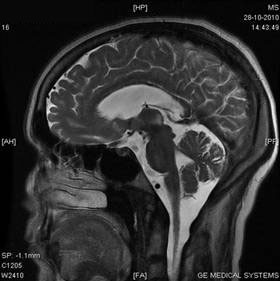

Beythien stemde in met een MRT met contrastvloeistof om op die manier te

kunnen zien of en waar er een eventuele vernauwing zou zitten.

De volgende foto’s spreken weer voor zich, alles zag er bijna goed uit